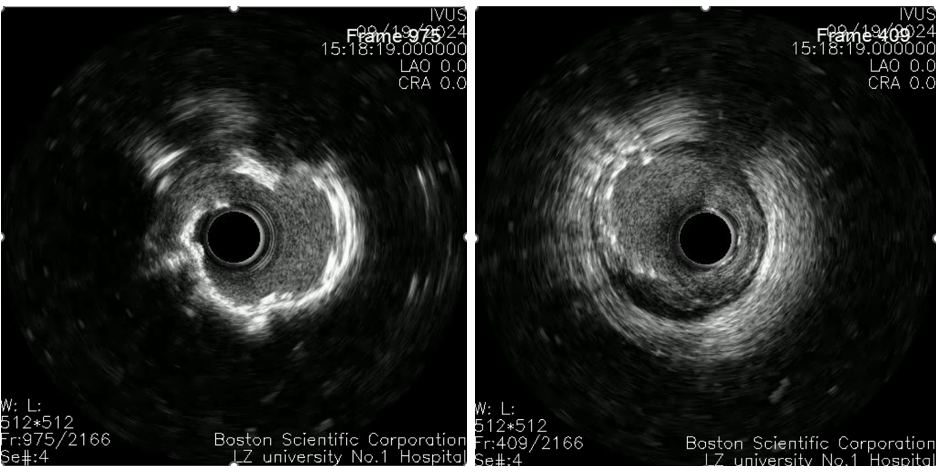

复查造影后再次复查前降支IVUS

前降支近中段支架膨胀不全;

遂3.5mm球囊高压扩张;

结合术后IVUS,考虑该处钙化严重及钙化小结导致IVUS导管及球囊无法通过。

复查造影支架贴壁良好

回旋支支架植入后因支架及钙化原因,IVUS导管无法推送至中段以后,遂仅对回旋支开口支架IVUS检查。

回旋支开口支架后扩后行IVUS检查:支架贴壁膨胀良好。